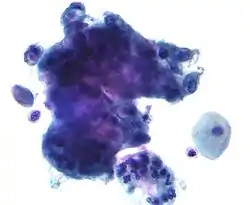

Micrograph of a normal pap smear